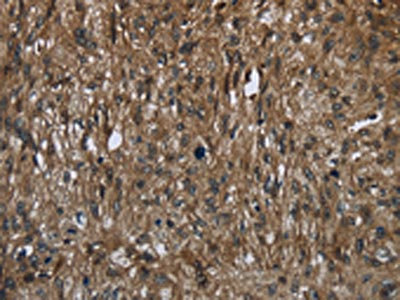

The image on the left is immunohistochemistry of paraffin-embedded Human cervical cancer tissue using CSB-PA566041(FASTKD2 Antibody) at dilution 1/50, on the right is treated with fusion protein. (Original magnification: ×200)

The image on the left is immunohistochemistry of paraffin-embedded Human esophagus cancer tissue using CSB-PA566041(FASTKD2 Antibody) at dilution 1/50, on the right is treated with fusion protein. (Original magnification: ×200)